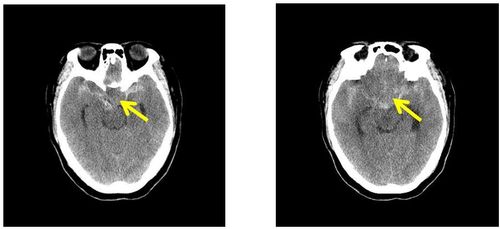

头颅ct检查提示:鞍区可见一类圆形稍高密度影,边界清晰锐利,以宽基底

头颅ct可见鞍区类圆形高密度影

昨天刚收的病人,以头痛就诊,无视神经损害症状,查头颅ct发现鞍区肿瘤